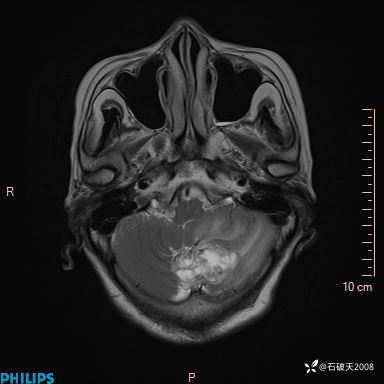

T2